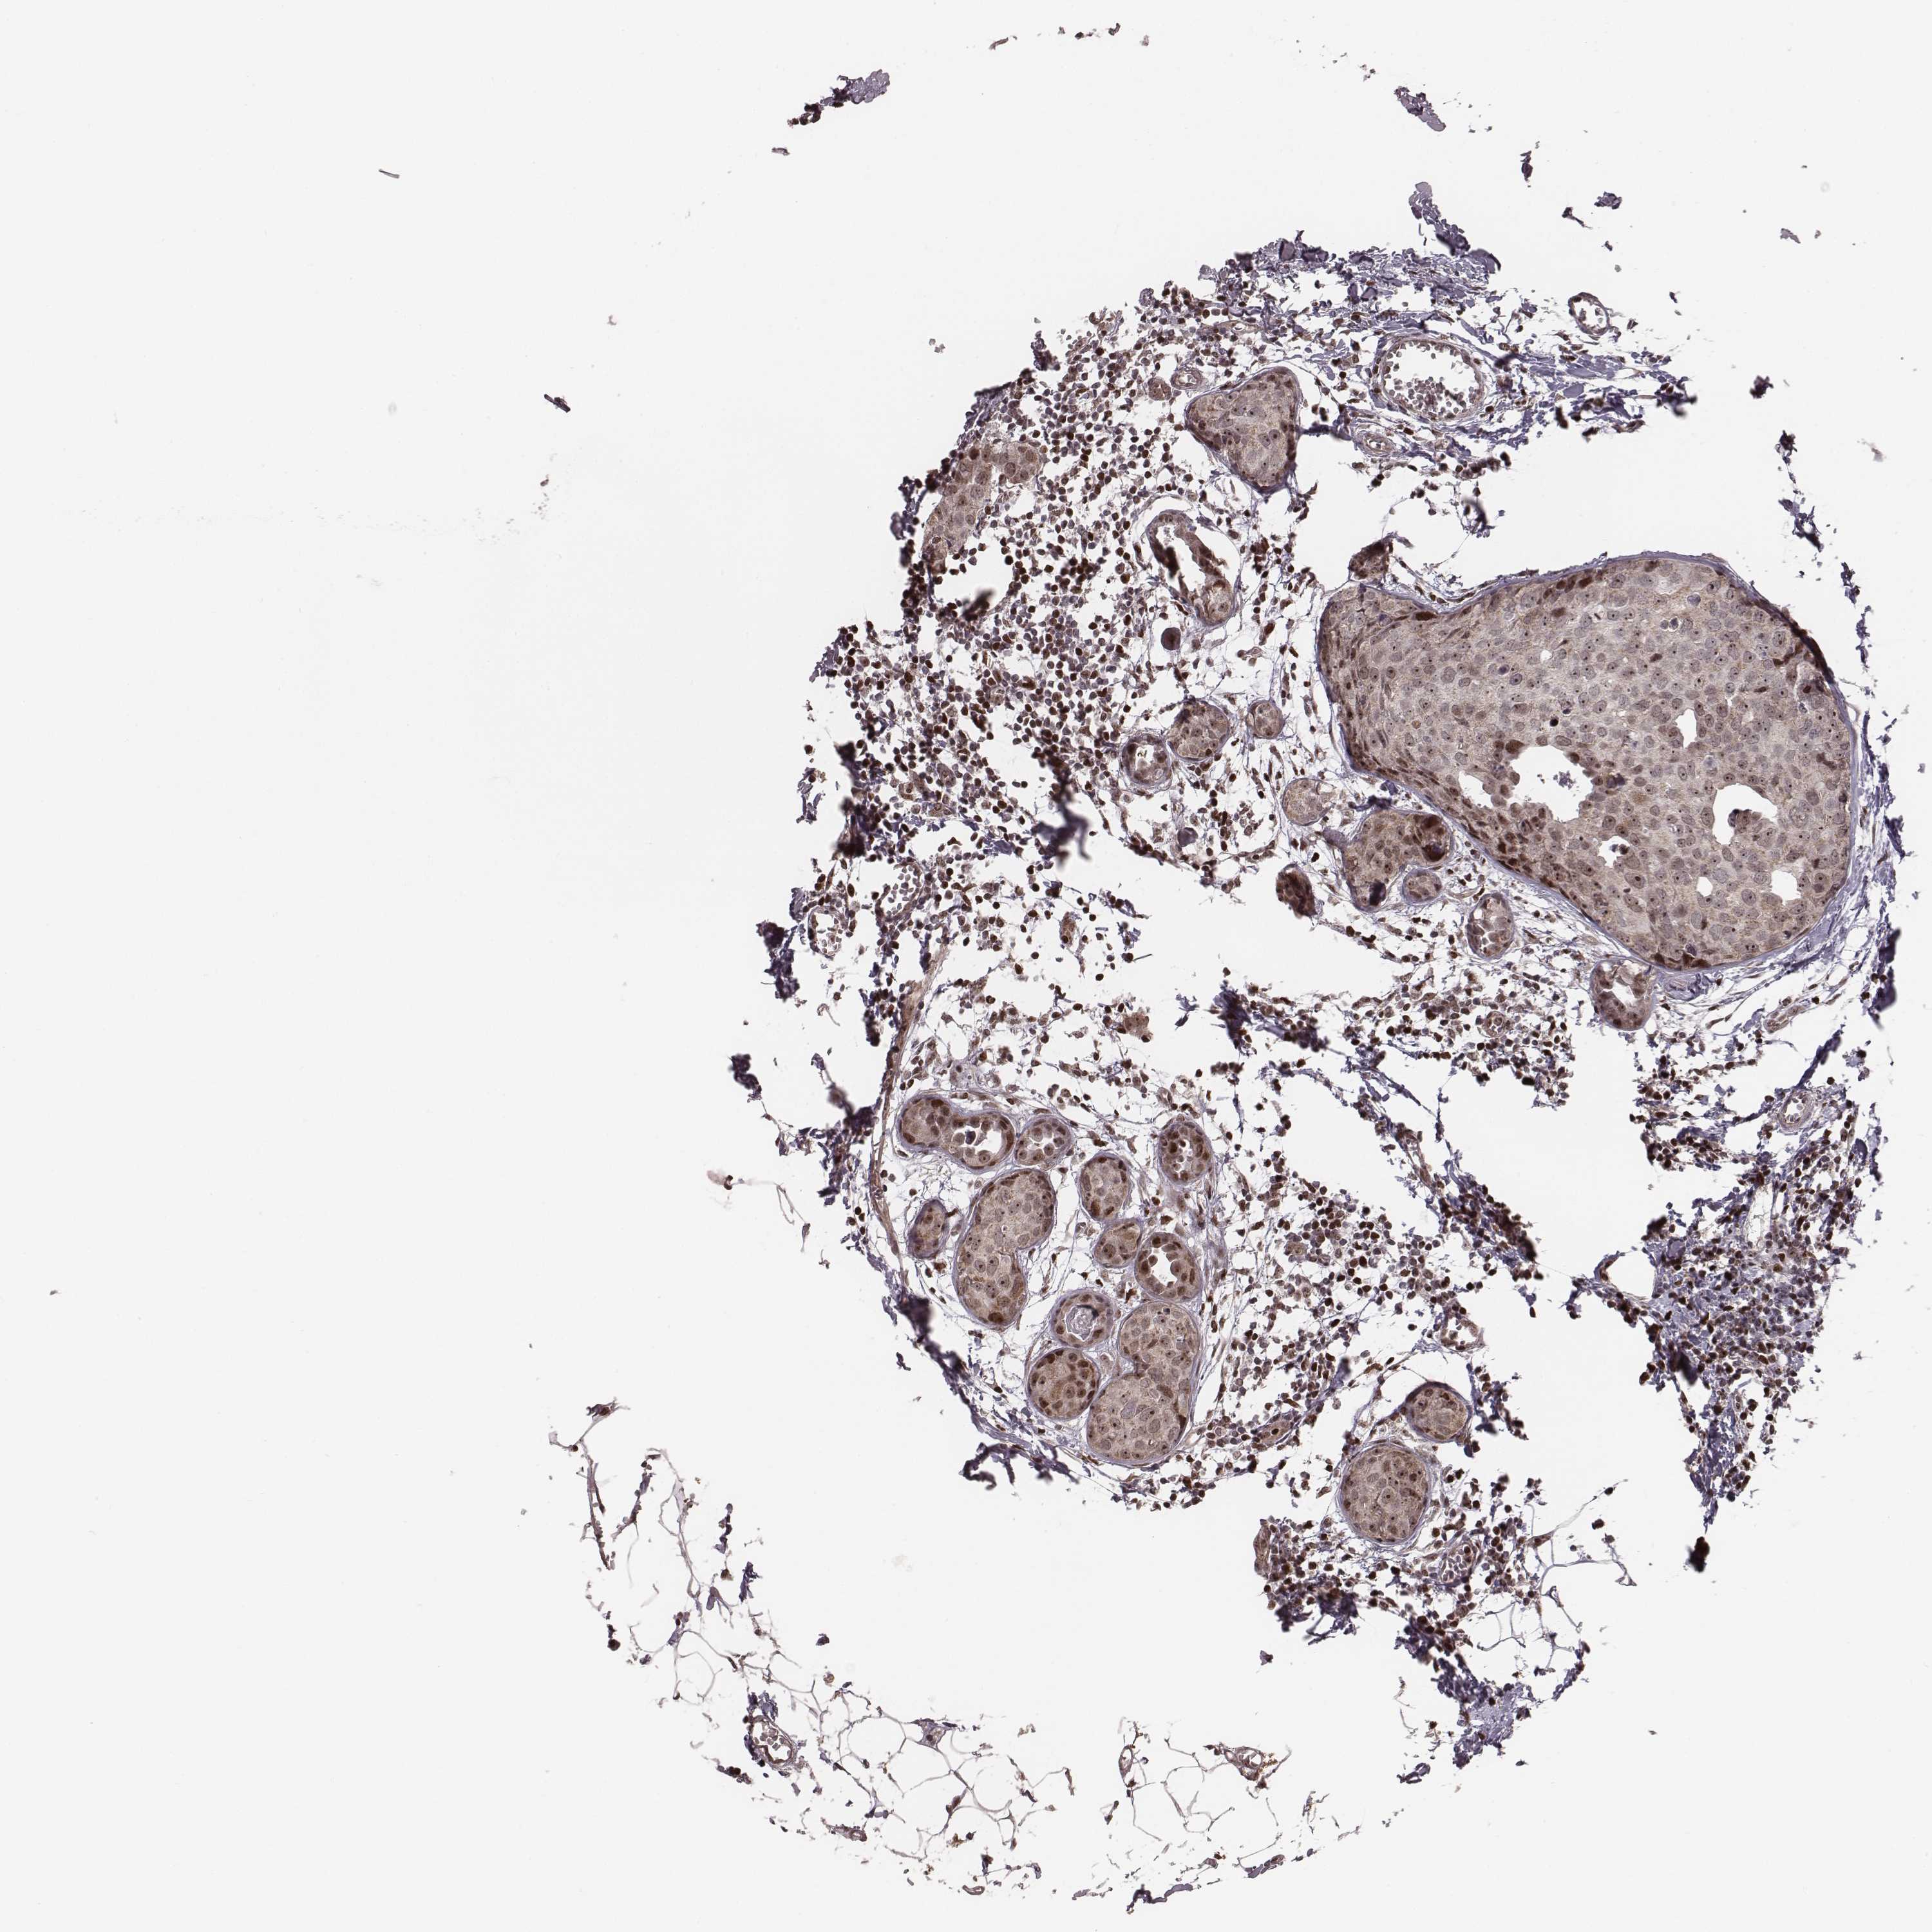

BRCA TCGA BRCA VALIDATION PROTEIN EXPRESSION